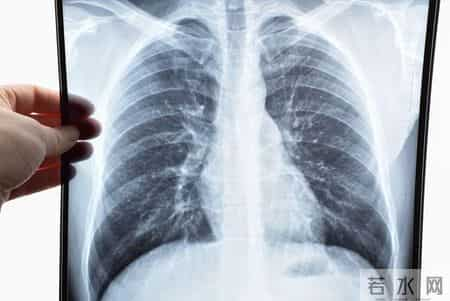

身边不少人年纪轻轻,咳嗽、喘不上气,动不动就“肺不舒服”?还有人总觉得胸闷,稍微爬个楼就累得不行。再一查体检报告,“肺功能下降”“慢性支气管炎”赫然在列。

有人说,肺是个“沉默器官”,坏得不声不响。但肺也很“争气”,只要你吃对、做对,它就能慢慢修复。今天我们就来聊聊,5种对肺好的食物,到底是怎么起作用的,是不是人人都适合吃,还有哪些日常习惯,正在悄悄伤害你的肺。

很多人以为“肺不舒服”只是感冒、咳嗽,其实很多时候是气道慢性炎症在作怪。就像一根被反复摩擦的吸管,时间久了,管壁就会变厚、变脆,通气也越来越差。

肺也一样,长期刺激,比如吸烟、污染、反复感染,会让肺功能一点点变差。